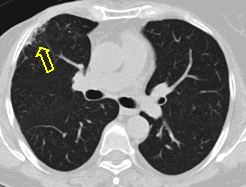

20. Miliary lung metastases. HRCT, coronal reconstruction:

60 year old man, secondary pulmonary lesions due to kidney tumor, underwent target therapy.

Lobulated nodule in the left lung, associated with the pleura dorsobasally.

Lobectomy because of right lung adenocarcinoma, (brain metastasis). (by the contribution of Zsuzsanna Monostori, MD, PhD)